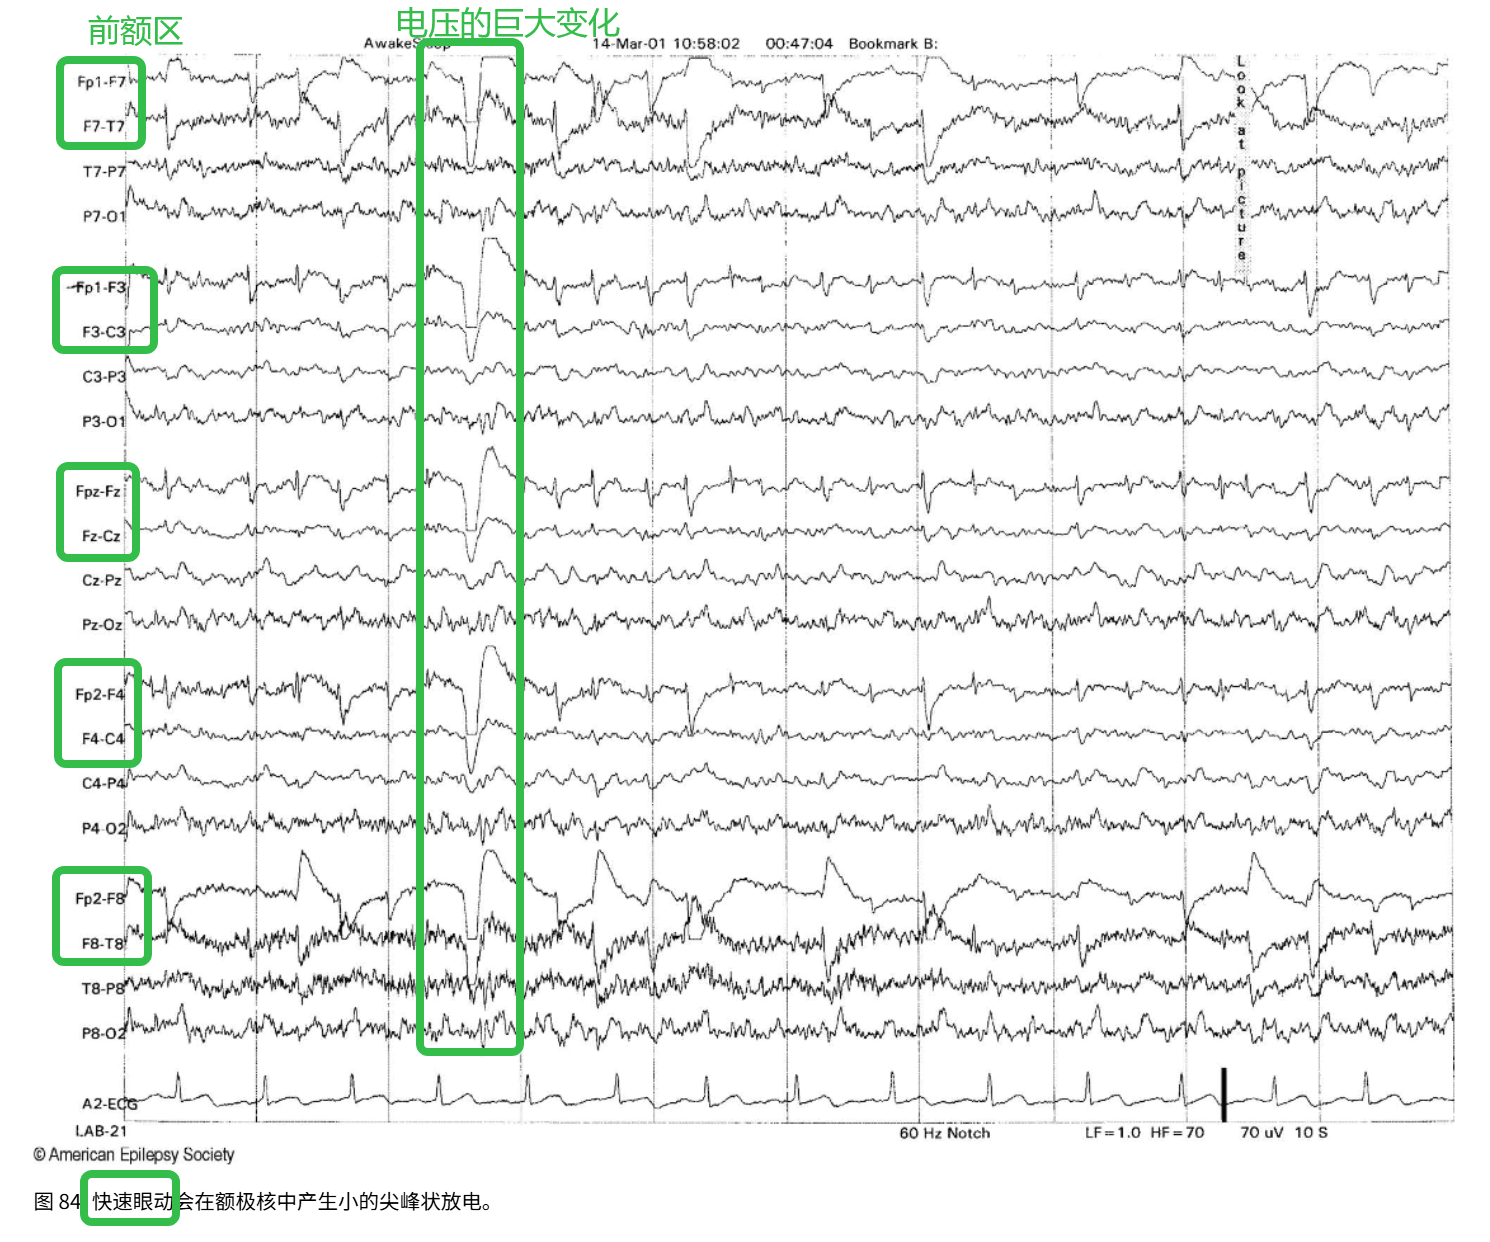

(3)快速眼动

来源:REM 睡眠期的快速、有节律的眼球运动

出现的位置:额极电极(Fp1/Fp2)、颞侧电极(F7/F8、T3/T4)

特征:显著的眼动电位变化